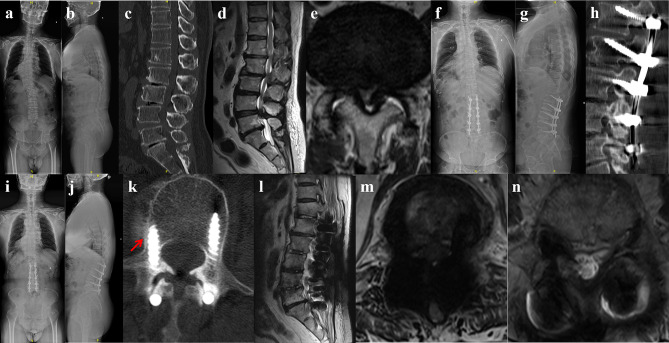

Patients and methods: From January 2018 to December 2019, a total of 41 patients of mild adult degenerative scoliosis with stenosis underwent posterior lumbar decompression, bone graft fusion, and internal fixation, which were retrospectively divided into pedicle screw (PS) group and cortical bone trajectory (CBT) screw group according to different internal fixation methods. The operation time, intraoperative blood loss, immobilization, and length of hospital stay were compared between the two groups. The visual analog score (VAS) of low back and leg pain, Oswestry disability index (ODI), Cobb angle, lumbar lordosis (LL) angle, apex vertebral translation (AVT), coronal balance distance (CBD) and sagittal vertical axis (SVA) were compared between the two groups preoperatively and 6 months, 1 year, 5 years postoperatively. Perioperative and follow-up complications were observed.

Results: The CBT group was superior to PS group in operation time, intraoperative blood loss, immobilization, length of hospital stay (P<0.05). The low back VAS and ODI in CBT group were significantly lower than those in PS group at 6 months, 1 year and 5 years postoperatively (P<0.05). The leg VAS in CBT group was lower than PS group at 5 years postoperatively (P<0.05). The incidence of screw loosening and adjacent segment disease 5 years postoperatively in CBT group was significantly lower than that in PS group (P<0.05).

Conclusion: Multi-segment cortical bone trajectory screws is a safe and effective treatment option for mild adult degenerative scoliosis with stenosis among the elderly. This technique features miniinvasive trauma and quick recovery, which might lead to improved long-term quality of life and a reduction in screw loosening and adjacent segment disease rates.